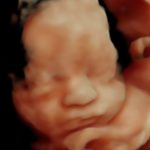

4D/5D/HD Ultrasound Gallery

Gallery